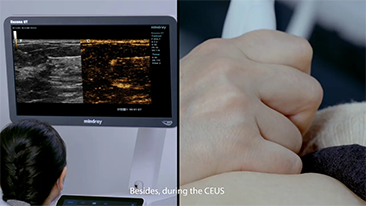

As solu??es de imagem geral Mindray Resona ajudam mĂŠdicos a obter resultados mais precisos e eficientes de diagnĂłstico e tratamento por meio de sondas de aplica??o de subdivis?es abrangentes e ferramentas eficientes de aplica??o clĂnica.

O ambiente mĂŠdico atual se tornou mais complexo, com um nĂşmero crescente de casos difĂceis e cargas de trabalho.